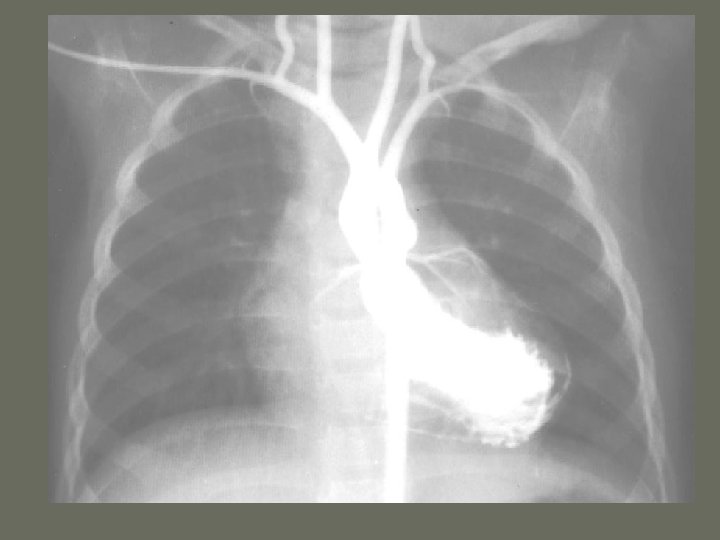

Cardiac Catheterization

Cardiac Catheterization • Angiocardiography 1. radiographic evaluation of the _______ of the heart and various valves 2. hemodynamic monitoring is the evaluation and recording of the function of the heart 3. include oxygen saturation, pressure tracings, and cardiac _______